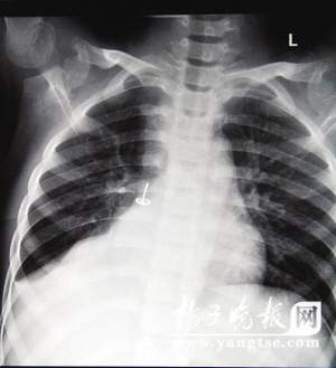

從片子上,圖釘在孩子右肺里“潛伏”得很深,卡在右下葉支氣管。南京市兒童醫(yī)院耳鼻喉科周艾醫(yī)生表示,由于圖釘堵住了孩子支氣管的通道,導(dǎo)致右肺葉不擴張,肺部已經(jīng)發(fā)生了實質(zhì)性的改變,用擴張來進(jìn)行氧氣交換的肺泡都已經(jīng)“癟”下去了,所以孩子的肺部功能非常弱。從片子上看,孩子的右肺已經(jīng)嚴(yán)重“萎縮”,比左肺小了一大圈。